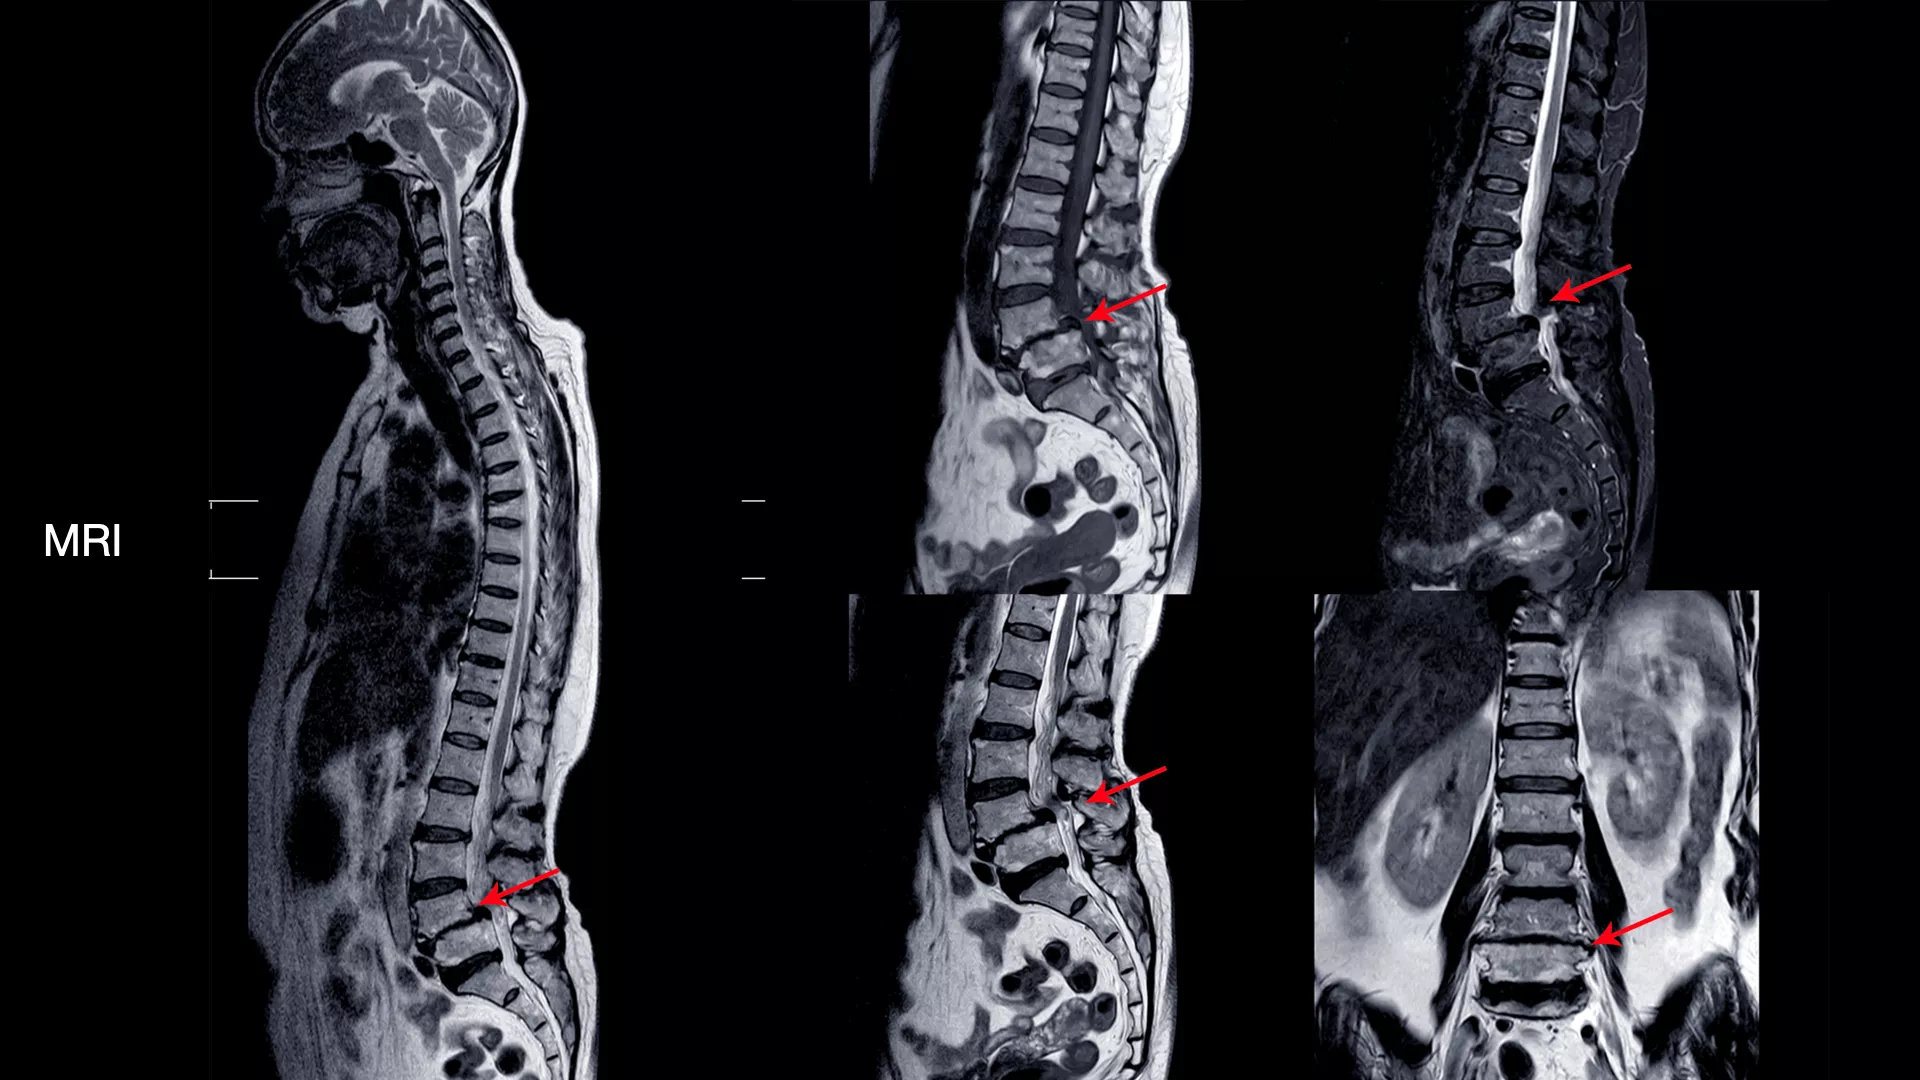

ดังนั้นการตรวจด้วย X-ray ทั้ง 4 ท่านี้จะช่วยให้แพทย์สามารถประเมินโครงสร้างของกระดูกสันหลังได้อย่างละเอียด และเป็นข้อมูลสำคัญในการพิจารณาแนวทางการรักษาที่เหมาะสมสำหรับผู้ป่วยแต่ละราย นอกจากนี้ การตรวจด้วย MRI (Magnetic Resonance Imaging) หรือ การสร้างภาพอวัยวะภายในร่างกายด้วยคลื่นแม่เหล็กไฟฟ้าและคลื่นวิทยุ โดยไม่ต้องใช้รังสีเอกซเรย์ที่เป็นอันตราย ก็มีความสำคัญอย่างยิ่งในการวินิจฉัยโรคกระดูกสันหลัง

เครื่อง MRI จะส่งคลื่นแม่เหล็กไฟฟ้าและคลื่นวิทยุเข้าไปในร่างกาย คลื่นเหล่านี้จะไปกระตุ้นโปรตอน (อนุภาคเล็กๆ ในอะตอม) ในร่างกายให้ปล่อยสัญญาณออกมา จากนั้นคอมพิวเตอร์จะแปลงสัญญาณที่ได้รับเป็นภาพ 3 มิติที่มีความละเอียดสูง ทำให้แพทย์สามารถเห็นรายละเอียดของเนื้อเยื่ออ่อนต่างๆ ได้อย่างชัดเจน

ดังนั้น การตรวจด้วย MRI จึงเข้ามาเติมเต็มในจุดนี้ โดยจะะให้ภาพที่มีความละเอียดสูงและสามารถเห็นรายละเอียดของเนื้อเยื่ออ่อนและลักษณะของรอยโรคได้อย่างชัดเจน ทำให้แพทย์สามารถ

- ระบุตำแหน่งและขนาดของรอยโรคได้อย่างแม่นยำ เช่น หมอนรองกระดูกปลิ้น หรือ หมอนรองกระดูกทับเส้นประสาท

- ประเมินความเสียหายของเส้นประสาท เห็นถึงระดับการกดทับของเส้นประสาทและไขสันหลัง

- วางแผนการรักษาได้อย่างถูกต้อง ช่วยให้แพทย์ตัดสินใจได้ว่าควรใช้วิธีการรักษาแบบไม่ผ่าตัด เช่น กายภาพบำบัด ทานยา หรือจำเป็นต้องผ่าตัด

การตรวจทั้ง X-ray และ MRI ร่วมกันจึงเป็นการผสมผสานที่สมบูรณ์แบบ เพื่อให้แพทย์ได้ข้อมูลที่ครอบคลุม ครบถ้วนและแม่นยำที่สุด สำหรับการวินิจฉัยและวางแผนการรักษาที่เหมาะสมสำหรับผู้ป่วยแต่ละราย